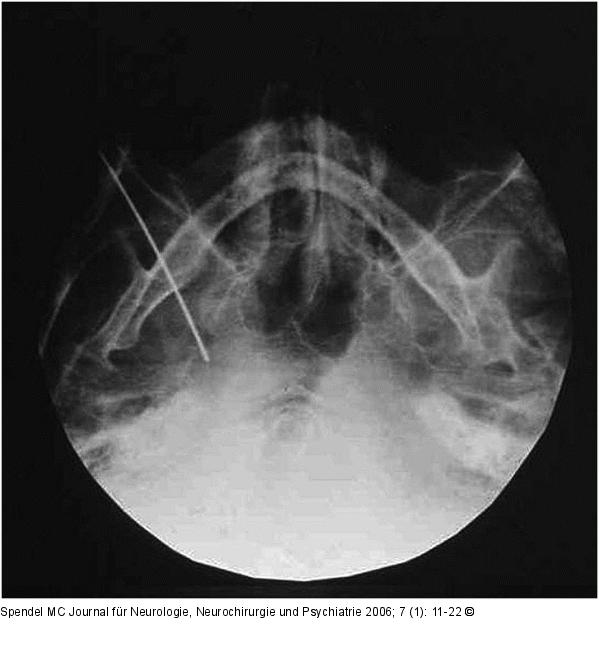

Abbildung 5: Elektrodenspitze - Foramen ovale Die submentovertikale Röntgenaufnahme der Schädelbasis zeigt die Elektrodenspitze im Foramen ovale rechts. |

Die submentovertikale Röntgenaufnahme der Schädelbasis zeigt die Elektrodenspitze im Foramen ovale rechts. |